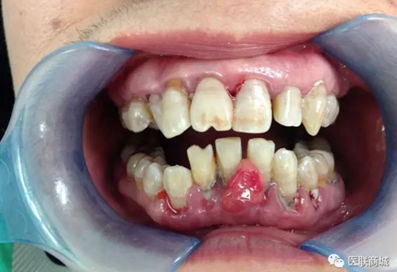

檢查:全口口腔衛(wèi)生差,牙齦紅腫,齦上牙石(+++),齦下牙石(+++),BOP(+),AL為3mm, BI=4,PD大于3mm,下中切牙間唇側可見如花生米樣大小腫物,碰觸出血,有蒂,基底寬,表面可見充血,下前牙松動一度。上下牙列不齊,下前牙間可見間隙。深覆牙合3度。

診斷:牙齦瘤 慢性牙周炎 治療計劃:向患者交待病情,需要拍攝全口曲面斷層片以協(xié)助診斷以及治療后的評估,查血以排除其它血液系統(tǒng)疾病,待血液檢查結果回來后,再行全口超聲潔治術及牙齦瘤切除術?;颊咭驗橘M用及時間等因素要求重新考慮后再行治療。后無復診。